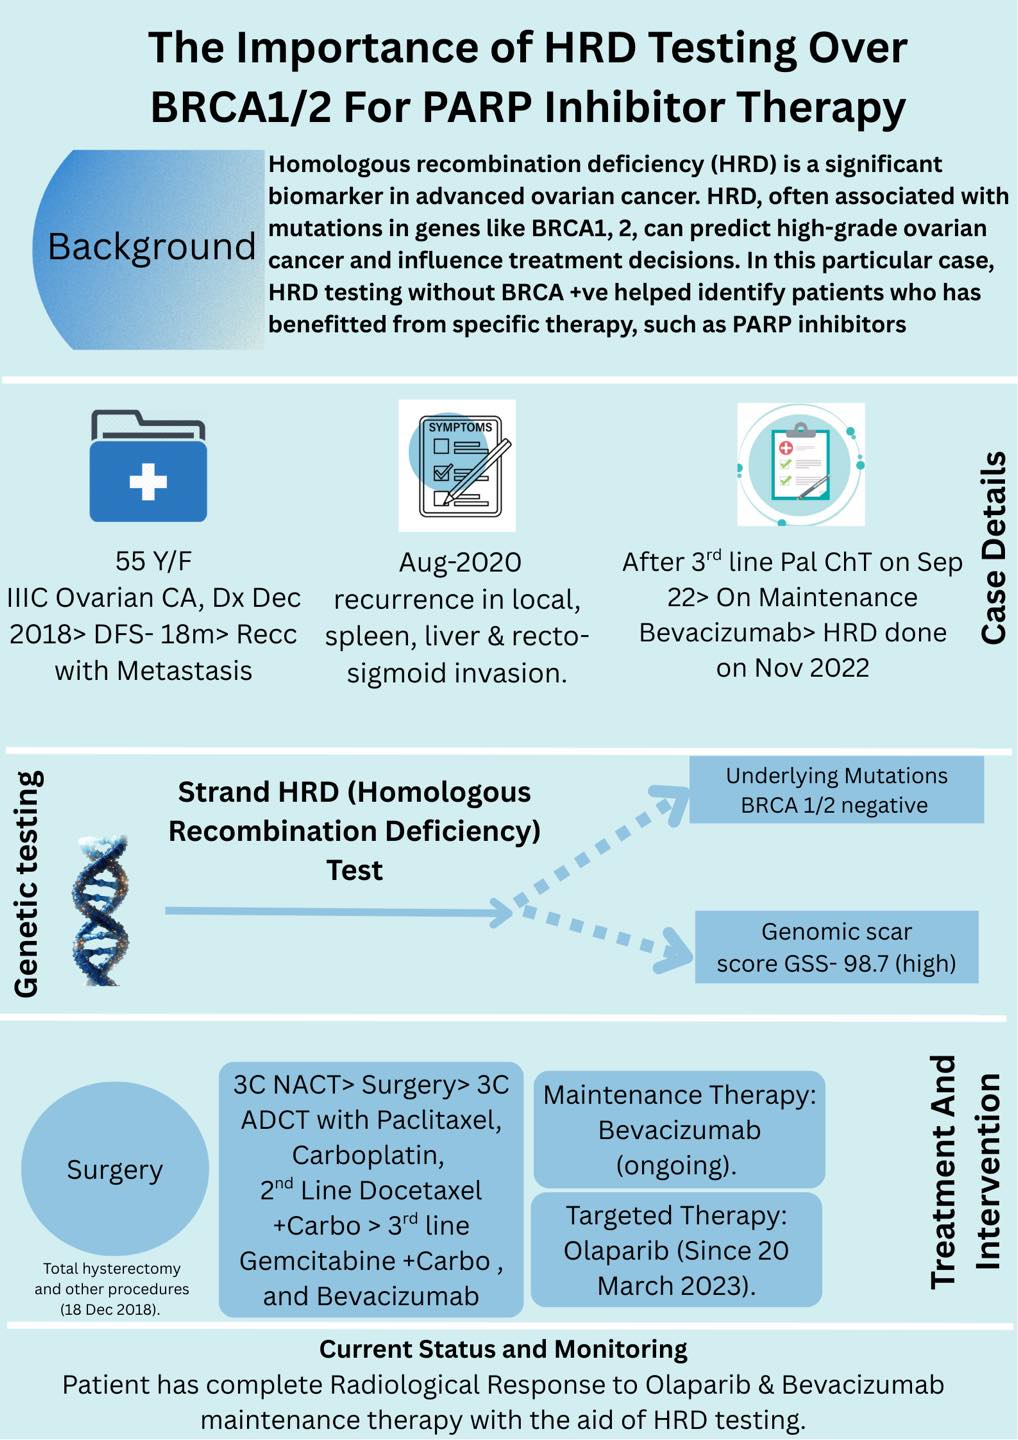

mOvarian Carcinoma Survivor

NA